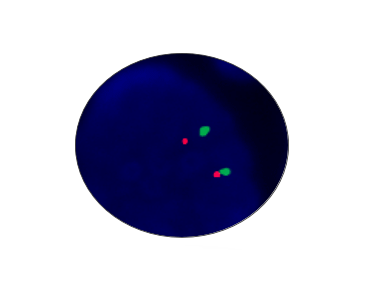

TERC Amplification

Probe Description: TERC/Cep3

Cat.No.: CF1030